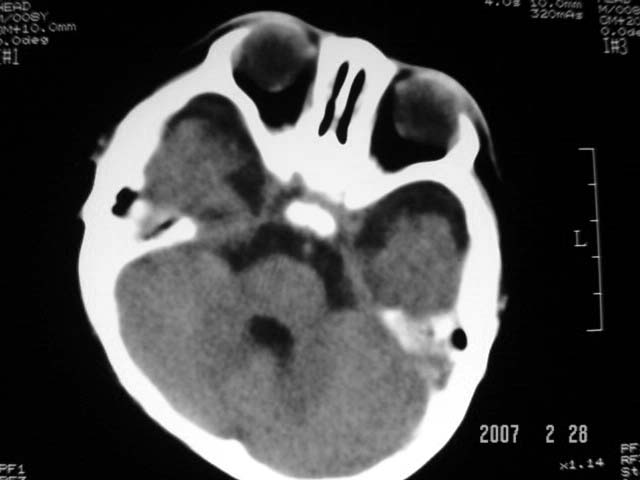

标题: PED0015:男,8M,发现不会坐立及神情异常,前囟已闭,双眼斜视,

脑回较深,白质范围小,灰白质比例失调。余未见明显异常。

考虑:脑白质发育不良,必要时请做mri进一步检查。